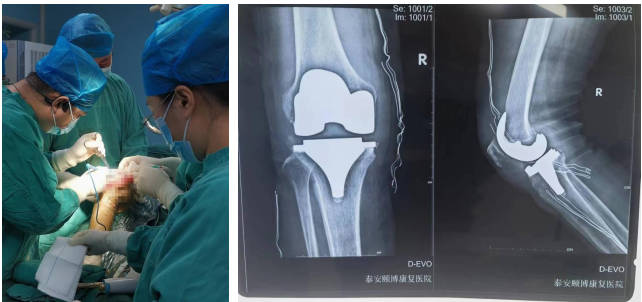

骨科

擅長(zhǎng)腰腿疼痛的診治及四肢骨折、外傷的救治。開展了全膝、髖關(guān)節(jié)置換術(shù)、肘內(nèi)翻、足外翻畸形矯形術(shù)、經(jīng)皮椎體成形術(shù)、復(fù)雜手足外傷皮瓣修復(fù)術(shù)、復(fù)雜關(guān)節(jié)內(nèi)骨折復(fù)位固定術(shù)、骨腫瘤切除植骨固定術(shù)、椎間孔鏡椎間盤髓核摘除術(shù)、椎管狹窄椎管減壓術(shù)。